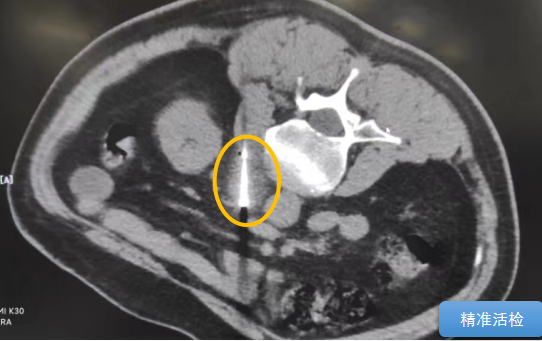

經(jīng)過多學(xué)科討論,陳寶瑩主任根據(jù)影像資料指出,患者轉(zhuǎn)移瘤位于腹膜后,內(nèi)側(cè)瀕臨人體最大的血管——主動脈;前方同樣有血管緊貼腫瘤;外側(cè)是腎臟,后方是椎體和神經(jīng),夾縫中進針難度大,治療時要避免周圍重要臟器、血管和神經(jīng)的損傷,因此可以選擇CT引導(dǎo)下精準(zhǔn)穿刺活檢同步冷凍消融治療,即獲得病理組織有利于下一步全身治療方案的調(diào)整,同時殺死腹膜后轉(zhuǎn)移瘤,周圍正常組織損傷的可能性也小。

術(shù)中陳寶瑩主任、李鐵柱教授、兀云飛醫(yī)生、魏東紅技師、汝平護士協(xié)調(diào)配合,夾縫進針難度雖大,但在CT引導(dǎo)下逐步進針,精準(zhǔn)到位,順利活檢取得組織,由于腫瘤較大,為了提高消融效率,平行置入兩根冷凍消融針,同時啟動冷凍消融,術(shù)中清晰觀察到冰球完全覆蓋病變,患者沒有任何不舒服,治療中還可以和醫(yī)生聊天。